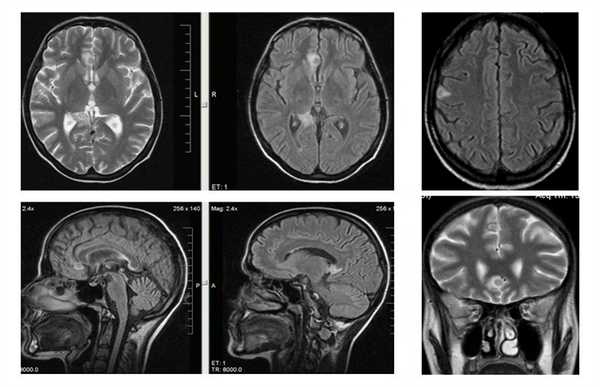

МРТ проявлениями первичного симптомокомплекса является диффузная атрофия с расширением желудочков, что приводит к прогрессирующей деменции и смерти.

МРТ головного мозга. Аксиальная Т2-взвешенная МРТ. Расширение борозд и диффузные очаги.

Прогрессирование атрофии при прослеживании МРТ головного мозга в динамике происходит очень быстро.

МРТ головного мозга. Т2-взвешенные аксиальные МРТ типа FLAIR. Динамика очагов за полгода.